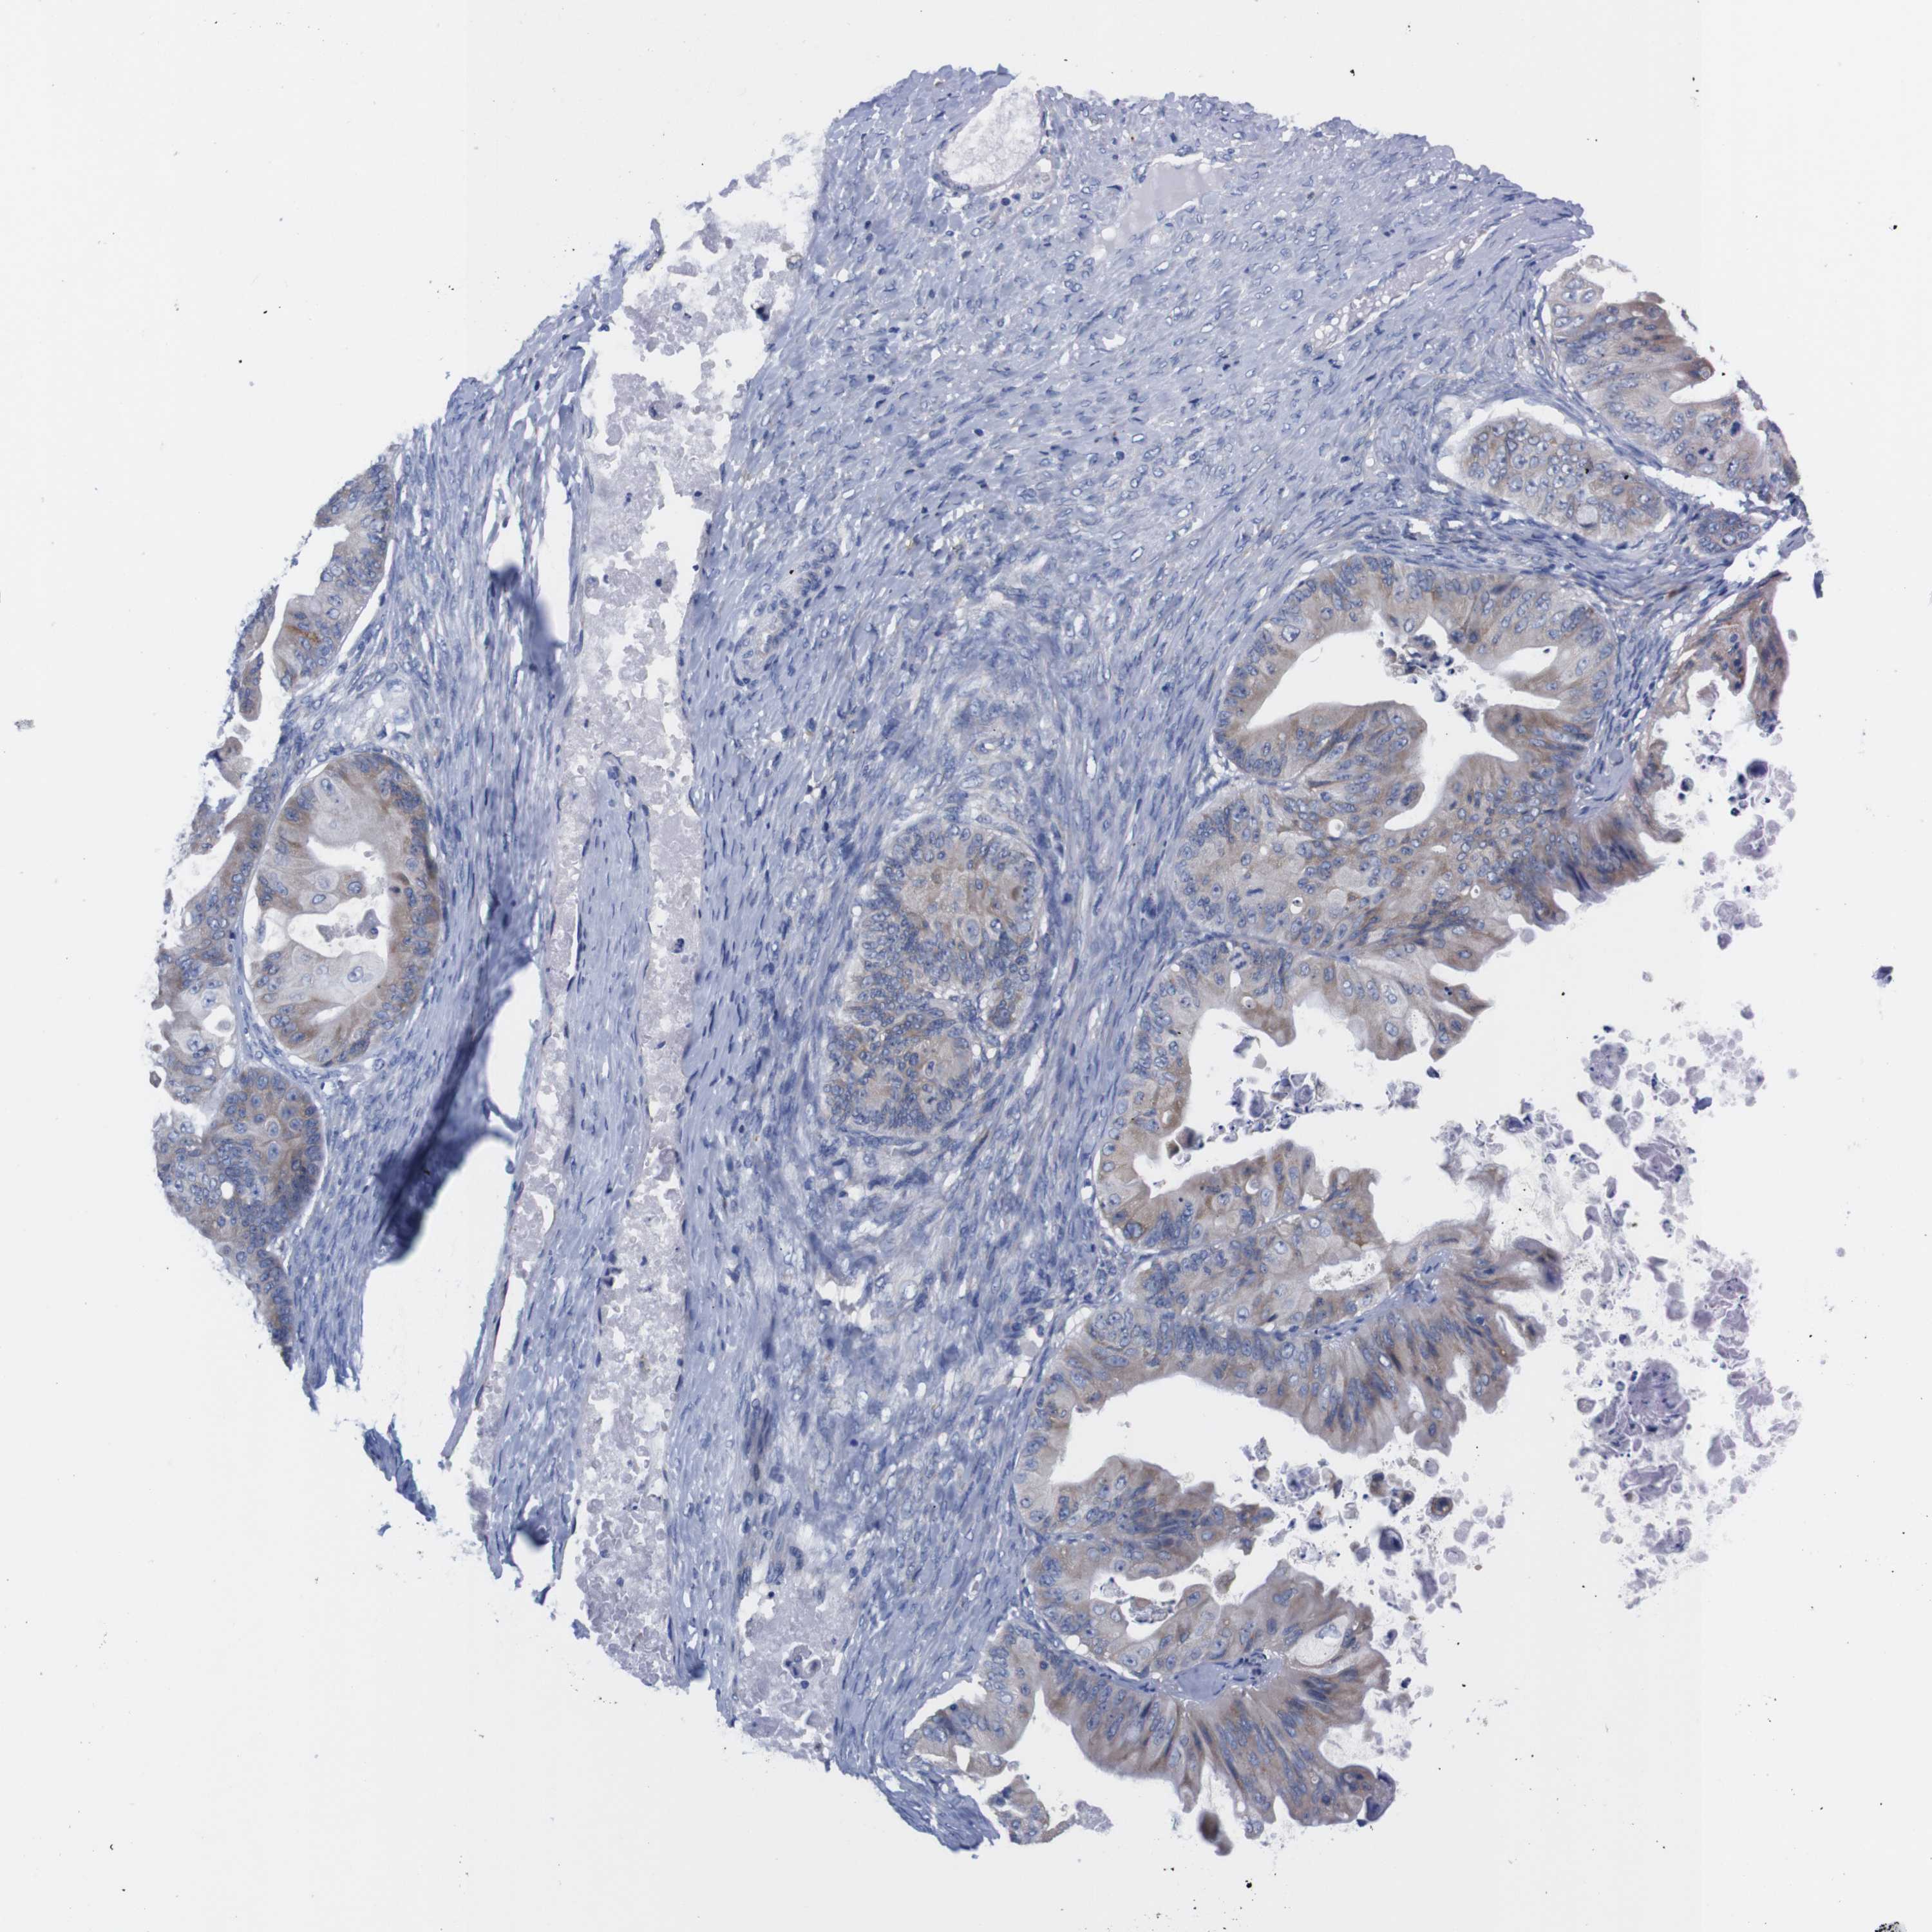

OVARIAN CANCER - Protein expressioni

A mouse-over function shows sample information and annotation data. Click on an image to view it in a full screen mode. Samples can be filtered based on level of antibody staining by selecting one or several of the following categories: high, medium, low and not detected. The assay and annotation is described here.

Note that samples used for immunohistochemistry by the Human Protein Atlas do not correspond to samples in the TCGA dataset.

Antibody stainingi

Antibody staining in the annotated cell types in the current human tissue is reported as not detected, low, medium, or high, based on conventional immunohistochemistry profiling in selected tissues. This score is based on the combination of the staining intensity and fraction of stained cells.

Each image is clickable and will lead to virtual microscopy that enables deeper exploration of all samples and also displays staining intensity scores, fraction scores and subcellular localization as well as patient and tissue information for each sample.

Antibody HPA013994

Antibody HPA013995

Cystadenocarcinoma, serous, NOS

Carcinoma, endometroid

Cystadenocarcinoma, mucinous, NOS

Carcinoma, NOS